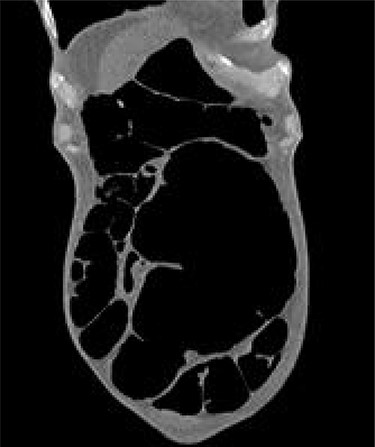

The patient continued to experience abdominal pain with multiple episodes of vomiting post-procedure. A wide-bore nasogastric tube was placed which drained 850 ml of bilious fluid. New onset tachycardia was noted and physical examination raised concerns for peritonitis. A further abdominal CT was performed which showed that the SV had been successfully decompressed but also revealed the presence of CV with proximal small bowel dilatation (Fig. 2). There was pneumatosis in the wall of the caecum which was distended to 10 cm in diameter, raising concerns for ischaemia and impending perforation. The patient was promptly transferred to the operating theatre for exploratory laparotomy.